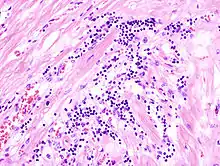

Acute myocardial infarction

Der Myokardinfarkt muss mind. 6 - 12 Stunden überlebt werden, bevor er morphologisch sichtbar wird!

Mikro: Koagulationsnekrose, Einblutungen. Die Myozyten zeigen eine verstärkte Eosinophilie und Kontraktionsbanden quer durch die Herzmuskelfasern. Typische Zellparameter wie Querstreifung, Zellkerne und Zellgrenzen gehen verloren. Das Infarktareal wird von einer Hyperämischen/hämorrhagischen Randzone begrenzt. Im Verlauf zunehmende leukozytäre Demarkation und Phagozytose des nekrotischen Gewebes, sowie Einwanderung von Fibroblasten mit Ausbildung eines narbigen Ersatzgewebes.

Makro: Lehmfarbene Abblassung mit hyperämischem/hämorrhagischem Randsaum.

![]() Akuter Myokardinfarkt, H&E. |

![]() Myokardinfarkt 7. Tag (Abräumphase), Sektionspräparat, H&E. |

![]() Akuter Myokardinfarkt, Kontraktionsbanden- nekrosen, PTAH. |